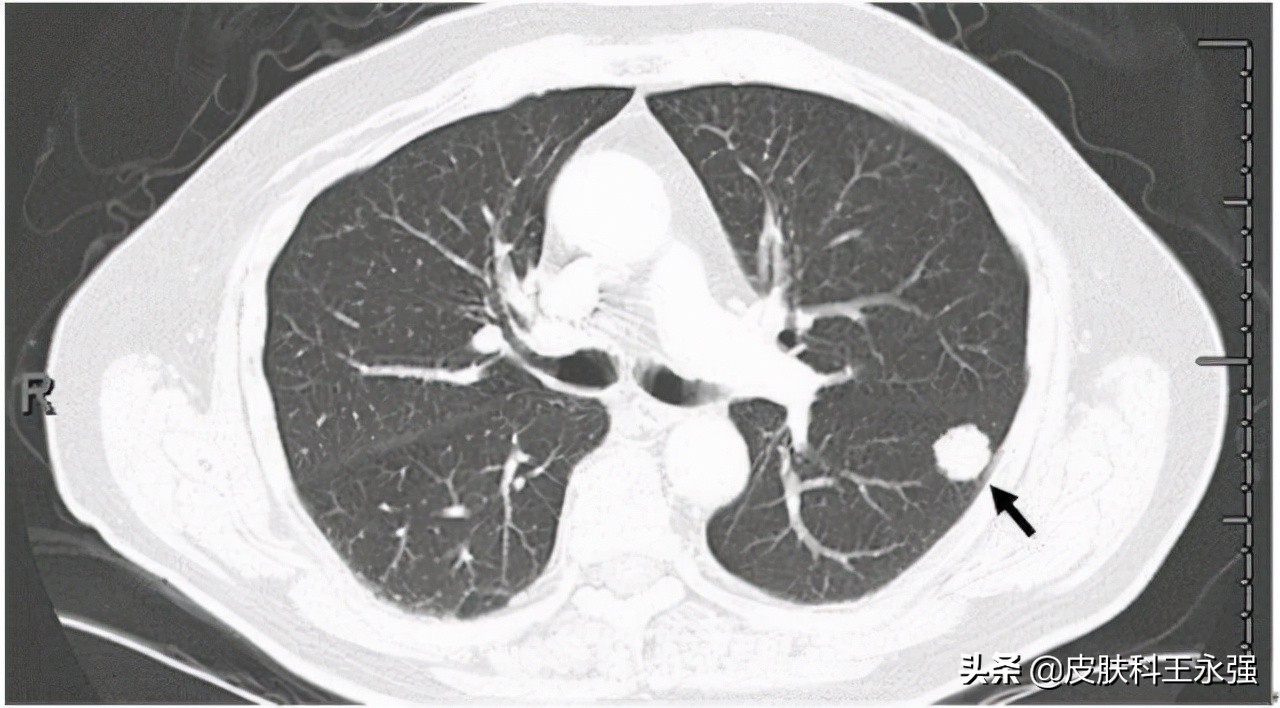

如果乳腺癌肺转移,就会存在肺结节,但是发现了肺结节,并不等于发生了乳腺癌肺转移。

倘若在乳腺癌发生之前,肺结节就已经存在,那基本上属于原发,排除转移的可能。而如果金女士所检查出的是肺部新增的结节,确实有转移的可能,而且可能性较大。这个时候需要综合的观察才能判断是原发的还是转移的。

而如果是肺部原发的肺结节,肺结核、炎性假瘤和肺部的局部炎症都可以引发肺结节。要检查结节是良性还是恶性,如果是原发性肺癌,需要定期观察随访。

肺结节,一般指直径不超过3.0cm的,类圆形或者是不规则形状的病灶,可以是单发,也可以是多个结节。根据结节的大小,5-10毫米的又被细分为肺小结节,而小于5毫米的叫做肺微小结节。直径超过3.0cm的,就称之为肺部肿块。

肺结节又分为实性结节和磨玻璃结节,磨玻璃结节包括纯磨玻璃结节和混合磨玻璃结节。其中,不透明的实性结节和半透明的混合磨玻璃结节恶性程度较高,需要尽早就医。纯磨玻璃结节虽然生长缓慢,风险较小,但也要注意,以免发展为混合磨玻璃结节。

肺结节,同样有良恶之分。但90%以上都是良性的。直径小于8毫米的大多为良性,20毫米以上的有半数概率是恶性的。而对于良性的肺结节也不能够掉以轻心,需要定期检查,避免不能及时发现结节异常的可能情况而延误病情。直径越大的结节发生异常,恶变的概率就会越大。同时,如果你存在长期吸烟、饮酒,或者肥胖等高危因素的话,癌变的风险就会增加,要及时预防感染。